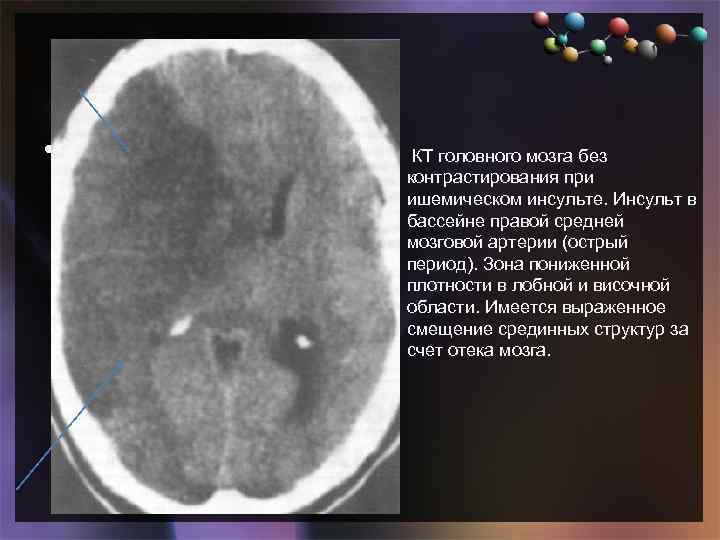

• Подзаголовок слайда КТ головного мозга без контрастирования при ишемическом инсульте. Инсульт в бассейне правой средней мозговой артерии (острый период). Зона пониженной плотности в лобной и височной области. Имеется выраженное смещение срединных структур за счет отека мозга.

• Подзаголовок слайда КТ головного мозга без контрастирования при ишемическом инсульте. Инсульт в бассейне правой средней мозговой артерии (острый период). Зона пониженной плотности в лобной и височной области. Имеется выраженное смещение срединных структур за счет отека мозга.